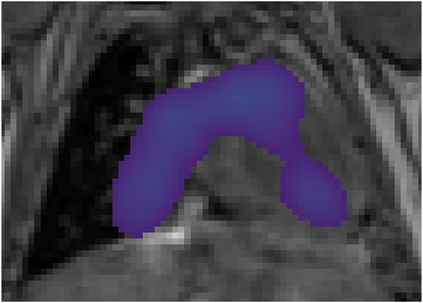

Various imaging modalities allow for time-dependent image reconstructions from measurements where its acquisition also has a time-dependent nature. Magnetic particle imaging (MPI) falls into this class of imaging modalities and it thus also provides a dynamic inverse problem. Without proper consideration of the dynamic behavior, motion artifacts in the reconstruction become an issue. More sophisticated methods need to be developed and applied to the reconstruction of the time-dependent sequences of images. In this context, we investigate the incorporation of motion priors in terms of certain flow-parameter-dependent PDEs in the reconstruction process of time-dependent 3D images in magnetic particle imaging. The present work comprises the method development for a general 3D+time setting for time-dependent linear forward operators, analytical investigation of necessary properties in the MPI forward operator, modeling aspects in dynamic MPI, and extensive numerical experiments on 3D+time imaging including simulated data as well as measurements from a rotation phantom and in-vivo data from a mouse.